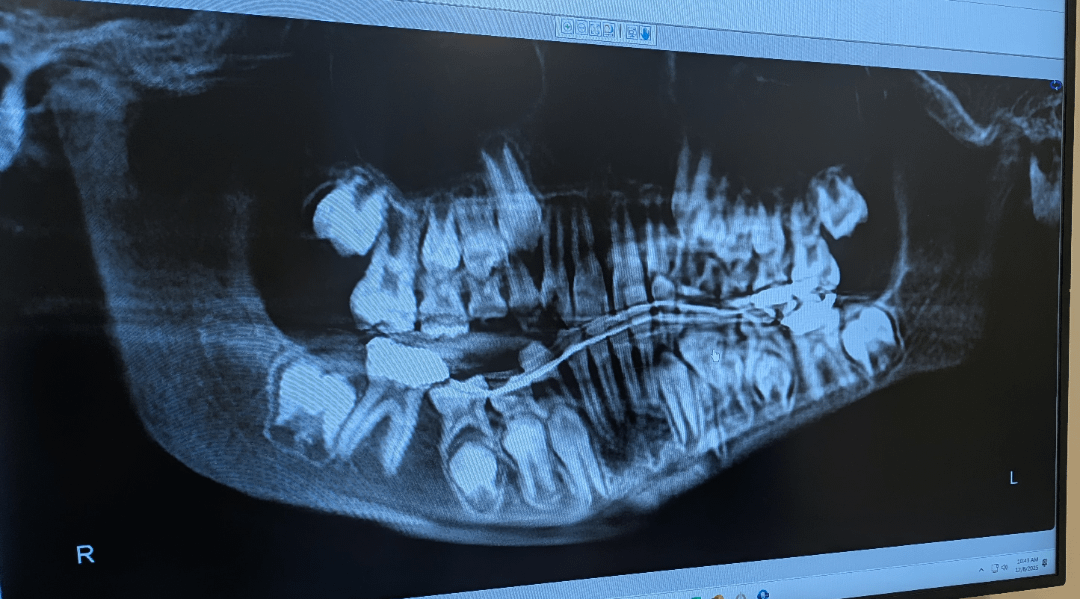

Most recent X-ray of my sons jaw

If your child has recently undergone an X-ray of their jaw, you likely have questions about what the scan reveals, why it was necessary, and what comes next. Jaw X-rays are critical diagnostic tools for pediatric dentists and oral surgeons, providing a clear picture of bone structure, tooth development, and potential abnormalities. In this guide, we’ll break down what a recent jaw X-ray might indicate, common concerns detected, and how to collaborate with healthcare providers for your child’s long-term well-being.

While only a dental professional can provide an accurate diagnosis, here’s what the most recent scan could show:

1. Tooth Development Issues

• Impacted Teeth: Adult teeth trapped beneath gums (common with wisdom teeth or canines).

• Delayed Eruption: Baby teeth blocking permanent teeth from emerging.

• Supernumerary Teeth: Extra teeth causing crowding or misalignment.

2. Bone Abnormalities

• Fractures: Hairline cracks from injuries.

• Osteopenia: Reduced bone density (rare in children).

• Cysts/Tumors: Fluid-filled sacs or growths requiring biopsy or removal.

3. Signs of Infection or Disease

• Abscesses: Pus-filled pockets near tooth roots.

• Periodontal Disease: Gum infection impacting bone (uncommon but possible in teens).

• TMJ Disorders: Jaw joint inflammation causing pain or limited movement.

4. Orthodontic Red Flags

• Malocclusion: Overbites, underbites, or crossbites.

• Crowding/Spacing Issues: Guides need for braces or expanders.